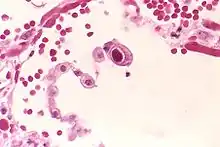

![]() | |

| An MRI showing a transverse myelitis lesion, which is lighter, oval shape at center-right. The patient recovered 3 months later. | |